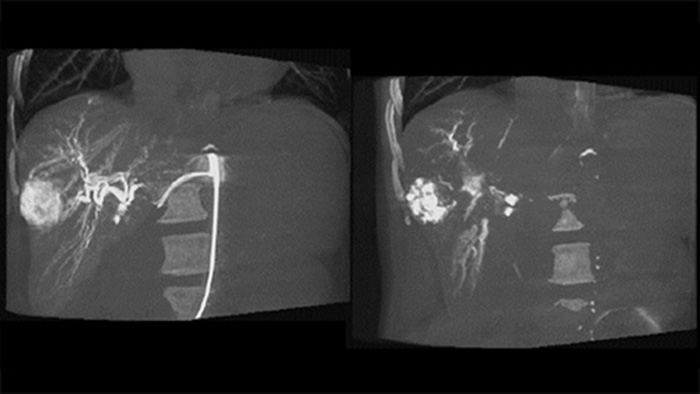

A post embolisation 3D acquisition allows you to visualise the targeted deposition of embolic material, such as Liopidol or radiopaque beads, in the tumor.5

Dual View allows simultaneous visualisation of pre-embolisation arterial phase 3D image and the post embolisation image to assess treatment endpoint.